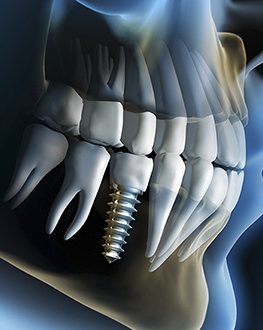

Implantodontia